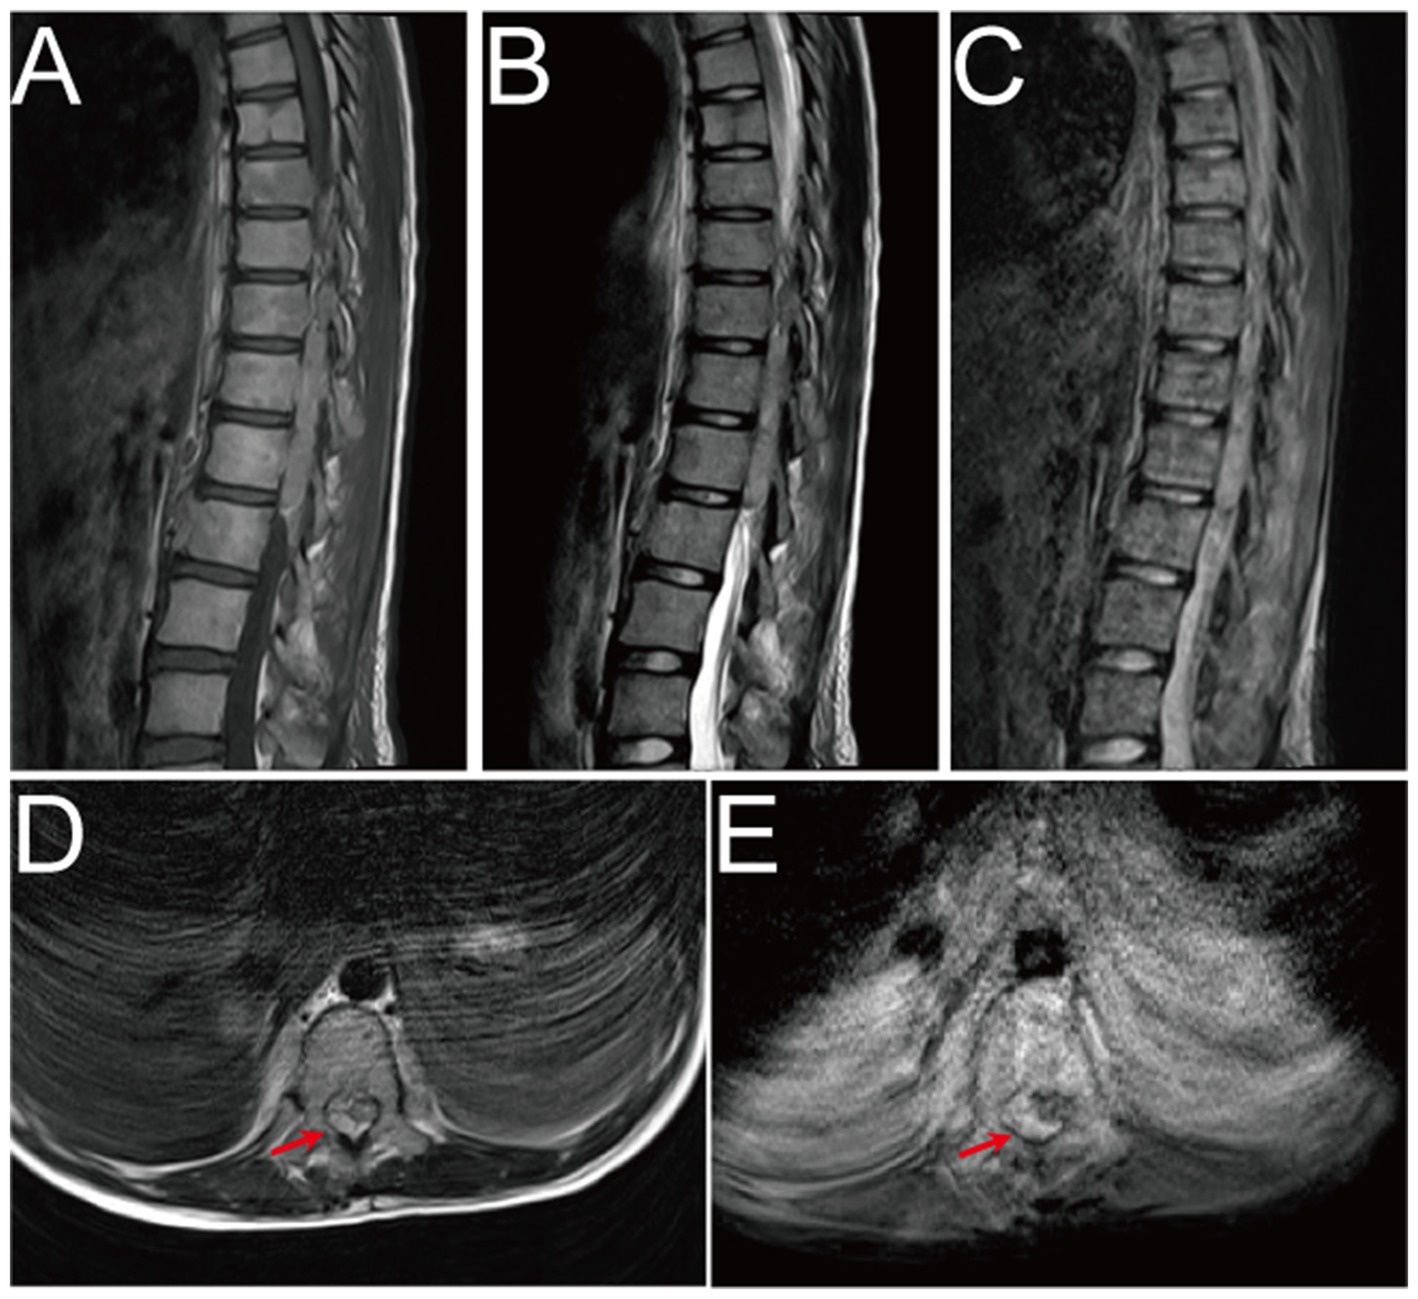

MRI scans of the spine and surrounding areas, labeled A through E. Images A, B, and C show sagittal views of the lumbar spine with varying levels of contrast and detail. Images D and E display transverse sections with a red arrow indicating a specific area of interest, possibly highlighting a lesion or abnormality.

Figure 2. Pre-operative MRI image. (A–E) Pre-operative MRI showed patchy heterogeneous signals in the vertebral body and appendages, and epidural hematoma at the T10-L1 level. The hematoma was crescent-shaped, measuring approximately 16 mm × 17 mm × 65 mm. Both T1WI and T2WI showed hyperintensity, while fat-saturation proton density-weighted sequences showed hyperintensity.

On Oct. 23, 2024, a 14-year-old female was urgently admitted to the emergency department (ED) with low back pain for 1 month, accompanied by systemic mucous membranes bleeding and ecchymosis for half a month, numbness and incomplete paralysis in both lower limbs for 3 days. One month ago, the patient suffered from lumbar pain due to an accidental sprain while running. Half a month ago, the back pain was further worsened after acupuncture on the latissimus dorsi muscles on both sides of the spine, accompained by swelling of the lumbar and buttock muscles, ecchymosis, and active bleeding gums. Fever appeared 4 days ago, with a maximum temperature of 38.5 °C, accompanied by acute urinary retention, the back pain worsened, and progressive decline in muscle strength of both lower limbs. After symptomatic conservative treatment such as antibiotics, analgesics drugs, and blood product transfusion, there was failure improvement in symptoms. No other special treatment. Parents are healthy, and there is no family history of genetic disease or similar disease. Physical examination: Forced high fowler’s position (60°–90°), severe malnutrition, anemia, pale systemic skin and mucous membranes, scattered in large areas of bruising and ecchymosis, especially in the lower limbs, slightly convex skin surface (Figure 1C). Both frontal nasal cavities have been tamponade to stop bleeding, the lumbar and buttock muscles are slightly swollen, and subcutaneous hematoma has formed. The movement of thoracolumbar and both lower limbs was significantly limited, the thoracolumbar and back tenderness and percussion pain. The grade muscle strength of both upper limbs, iliopsoas muscle, quadriceps femoris, tibialis anterior and extensor hallucis longus were 5-/5, 3-/5, 3-/5, 0/5, and 0/5, respectively. Sensation in the perineum and below the plane of the inguinal region was significantly reduced. Active range of motion (AROM) in bilateral lower extremities: hip flexion 0°–45°, knee flexion 0°-90°, ankle dorsiflexion 0°. Brudzinski sign (−), Kernig sign (−), and Babinski sign (−), absent tendon reflexes, ankle and patellar clonus (The child was unable to tolerate physical examination due to severe pain.). Laboratory data: white blood cell (WBC) 4.27 × 109/L, red blood cell (RBC) 2.62 × 1012/L, hemoglobin (HGB) 79 g/L, platelet (PLT) 24 × 109/L, prothrombin time (PT) 16.20s, activated partial thromboplastin time (APTT) 46.90s, D-dimer >20 mg/L FEU (Table 1). Radiographic data: MRI (magnetic resonance imaging): T11-L1 epidural irregular abnormal signals in the spinal canal, with a range of about 16 mm × 17 mm × 65 mm (Figures 2AE). Based on the above clinical and imaging presentations, the diagnoses of Thoracolumbar spinal epidural hematoma with bilateral lower limb incomplete paraplegia (ASIA-C, T10-L1), DIC (ISTH overt DIC score: 5 points), Febrile fever of unknown origin (FUO), and Traumatic iliopsoas hematoma formation were made. Hematonosis, infection, autoimmune, syndrome of cauda equina (SCE), or malignancy, such as primary or metastatic epidural tumor, were included in the differential diagnosis. At the time of examination (3 days after onset), reflexes were absent, possibly due to acute cord compression; however, as evolution over time was not documented, further histochemical and histopathological examinations were necessary for differential diagnosis. Given that the patient did not exhibit the typical signs of cauda equina syndrome—which is characterized by a flaccid bladder and overflow incontinence—this diagnosis was excluded. The evacuation of T10-L1 epidural hematoma and expanded decompression of spinal canal were performed. The surgery procedure involved resection of the entire lamina at T10 and the right lamina at T11-L1, revealing, as anticipated from the pre-operative MRI, a hematoma situated on the right side of the spinal canal, which substantially compressed the spinal cord, resulting in minimal dural pulsation (Figure 1B). Then, the evacuated hematoma was sent for routine pathology (Figure 1D). Post-operatively, there was no significant improvement in systemic symptoms. The post-op bone marrow aspiration biopsy showed active proliferation of bone marrow, with more basophils and phagocytes. Unknown cells accounted for 77.00%, and myeloid sarcoma or mast cell leukemia was suspected, while neuroblastoma cell nature could not be excluded. There was a positive immunohistochemical reaction of CD117 and Ki-67, with negative results for the other markers tested in the pathological tissue from the post-op epidural hematoma and bone marrow aspiration biopsy. Combined with flow cytometry, histomorphology, and immunohistochemistry, leukemia was highly suspected. However, as the patient’s condition showed no significant improvement, it was deemed necessary to thoroughly reassess the medical history and conduct a detailed physical examination. It was noted that the child had a large cauliflower-like black mole on the right scalp since childhood, which repeatedly ulcerated and failed to heal (Figure 1A). Subsequently, immunohistochemical staining for MM- related markers on bone marrow and hematoma specimens was conducted, and the results showed positive staining for HMB45, Melan-A, SOX10, S100, and PRAME, with negative results for the other markers. Based on the patient’s scalp lesion, combined with positive immunohistochemical (IHC) staining for tumor markers in both the intraoperative hematoma specimen and the post-op iliac bone marrow biopsy, the results confirmed the diagnosis of MM. However, despite 2 months of aggressive symptomatic and supportive treatment, the child ultimately succumbed to MM forever.

To our knowledge, this case is exceptionally rare, as DIC was triggered by MM bone marrow infiltration, and even more unusual is the presence of SEH within the thoracolumbar spinal canal on MRI. SEH is a rare yet potentially fatal disease, with an incidence <1/1000000, accounting for about 1% of spinal epidural space-occupying lesions (49). Over the past 3 years, around 1,000 cases have been documented in the literature worldwide. Common etiologies include trauma, coagulopathy, drugs, hypertension, arteriovenous malformations or spinal puncture. Hematoma typically occur in the dorsal cervicothoracic and thoracolumbar segments, with typically manifests as patients severe knife pain at the site of hemorrhage, and some may experience painless intervals, followed by progressive paralysis below the affected spinal cord level (7, 8, 50). MRI is the preferred imaging modality when SEH is suspected. In acute phase (<24 h), T1-weighted images showed isointensity, while T2-weighted images demonstrate hyperintensity. In subacute phase (>24 h), both T1 and T2-weighted images showed hyperintensity. In chronic phase, both T1 and T2-weighted images showed hypointensity. Fat-saturation proton density-weighted images were used to distinguish hematoma from epidural fat (51). A consensus from most reported cases suggests that once SEH was diagnosed, emergent or at least urgent surgical intervention is necessary, with earlier intervention leading to a better prognosis. Besides, pre-operative neurologic status is also a critically important prognostic indicator (50, 5254). Therefore, once MM bone marrow infiltration with SEH was diagnosed, surgery (hemilaminectomy or laminectomy with irrigation and debridement) or conservative management based on the imaging data and neurologic status should be selected as soon as possible (52). In this case, despite urgent surgical intervention and subsequent systemic treatment for MM, the outcome was unfortunately unsatisfactory, and succumbed to the disease, after 2 months.